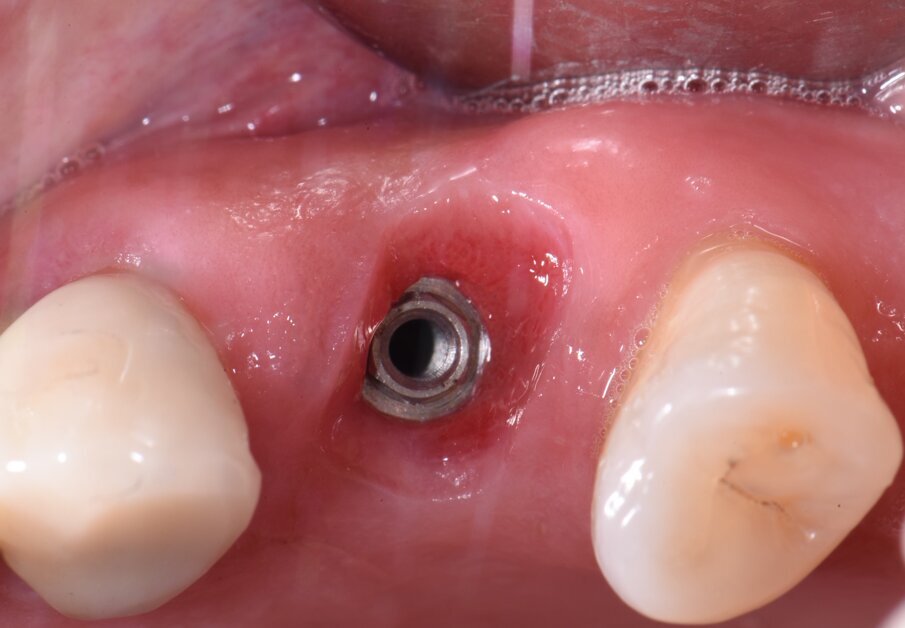

Tre mesi dopo, l’inserimento dell’impianto i volumi anatomici dei tessuti perimplantari presentano la stessa forma e dimensione di quella precedente dell’estrazione del dente (Fig. 3). Dopo il rilevamento dell’impronta digitale si disegnano i margini gengivali del manufatto protesico, prestando attenzione al profilo d’emergenza (Figg. 4a, 4b). La corona in disilicato di litio viene cementata rispettando i profili anatomici conservati dalla cappetta castomizzata (Fig. 5). A distanza di due anni si possono notare il mantenimento volumetrico delle strutture tessutali attorno al restauro implant-protesico.

Fig. 3 - Si può notare il trofismo e il volume dei tessuti periimplantari 3 mesi dopo l’inserimento dell’impianto.